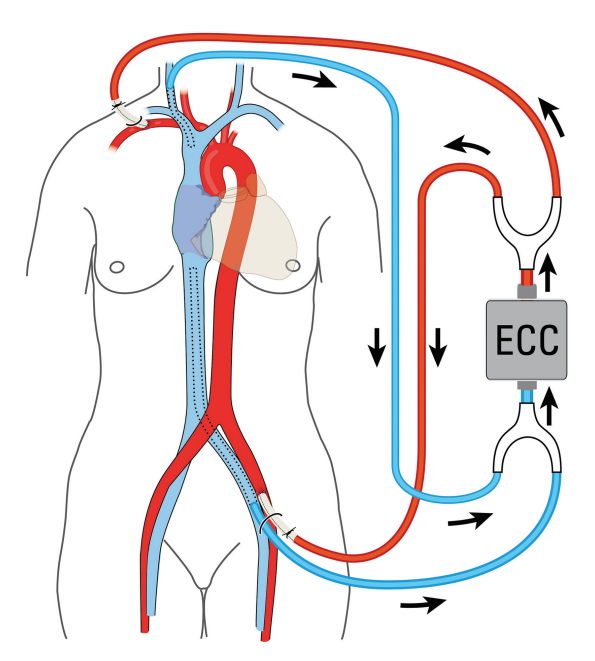

由于严重的肺阻塞和可能的脓毒性栓塞,安排了紧急手术。通过右锁骨下动脉和左股动脉建立动脉插管。两条动脉都显示出小的管腔,单独使用一条动脉无法提供足够的旁路流量。出于同样的原因,两条动脉都不适合直接插管。因此,需要两个 7mm的镀银假体进行动脉连接。通过左股静脉和右颈静脉进行经皮静脉插管。后者是必要 的,因为上腔静脉完全血栓形成,而且不可能单独通过股静脉插管进行上腔静脉引流。体外循环(CPB)连接如图所示(图2)。降温至 30℃再入胸腔后,发现胸骨柄附着6× 7 cm炎性肿块。脓肿腔打开,显露同种移植物坏死。假体前壁因感染坏死。一个1.3×3cm 的血栓完全阻塞了同种移植物瓣膜。脓毒性血栓延伸至右肺动脉。小心地取出同种移植物血栓,用吸盘取右肺动脉局部血栓。离体组织如图所示(图3A)。手术清创后,用KerraSol (Crawford Healthcare GmbH, Valley, 德国)冲洗伤口。在RVOT植入25mm的Medtronic plc.Freestyle根部生物瓣膜(Medtronic plc., 都柏林,爱尔兰) (图3 B)。

图2. 体外循环连接示意图。ECC,体外循环。

即使在治疗成功后,真菌性心内膜炎的复发率仍高达30%。目前的指南建议对真菌性心内膜炎进行手术和药物联合治疗。在这种情况下,一些外科方面值得更多的关注。为了第五次手术时灌注的安全可靠,在胸骨重开之前建立 CPB。由于股动脉小,需要额外的锁骨下通路。由于口径小,对移植假体行吻合术。由于上腔静脉血栓形成,需要通过颈静脉进行额外的静脉引流(图3)。需要跳动心脏手术,因为大量的粘连使得主动脉交叉夹持的准备工作要求高,耗时长。选择美敦力自由式假体是由于其作为先天性心脏手术的一部分植入 RVOT 时具有良好的效果。冠状动脉起始处缝合并置于腹侧,以避免移植物扭结。出于相同的原因,在假体的上缘和肺分叉之间额外插入了一个牛补片。